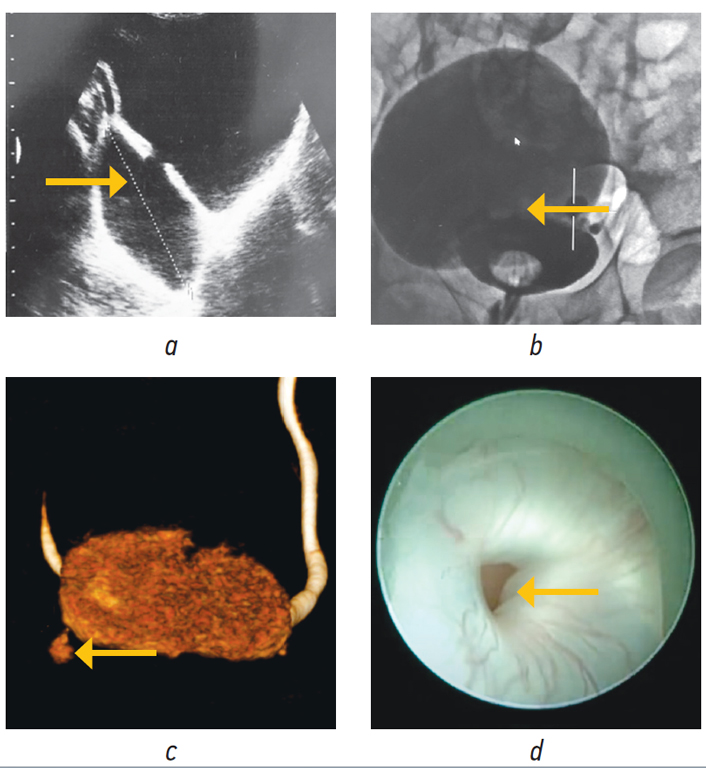

Диагностика ДМП обычно не составляет труда и включает такие инструментальные методы, как ультразвуковое исследование, компьютерная (магнитно-резонансная) томография малого таза с контрастным усилением, цистография и цистоскопия (рис. 1).

Рис. 1. Методы визуализации дивертикулов мочевого пузыря: a — ультразвуковое исследование мочевого пузыря; b — нисходящая цистография; c — компьютерная томография с 3D-реконструкцией; d — цистоскопия. На рисунках a, b и c стрелками указаны дивертикулы мочевого пузыря, на рисунке d стрелкой указана шейка дивертикула мочевого пузыря / Fig. 1. Methods of visualization of bladder diverticula: a — ultrasound examination of the bladder; b — descending cystography; c — computed tomography with 3D reconstruction; d — cystoscopy. In Figures a, b, and c, the arrows indicate bladder diverticula; in Figure d, the arrow indicates the neck of the bladder diverticulum